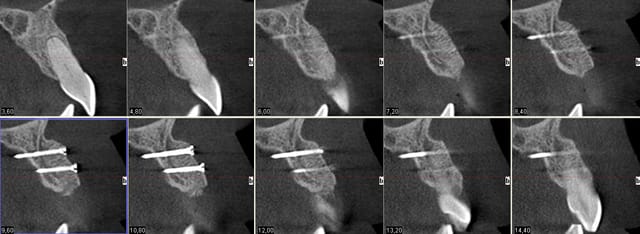

19/08/2011 à 15h42

au fait, suite à ce cas:

réouverture ce matin, le volume obtenu par la greffe est conservé, os densité D2-D3.

Coupe verticles dv3vle - Eugenol

Coupe horizontale ns9kzl - Eugenol

3d l4bhde - Eugenol

3drecons jubvki - Eugenol

3d1 x4onsj - Eugenol

Greffe3d xbwyhk - Eugenol

L implantn eftzk3 - Eugenol

il est effectivement assez réjouissant, à chaque réouverture, de retrouver un volume identique à celui obtenu le jour de la greffe. De plus, la densité est suffisante pour obtenir une stabilité primaire compatible avec de la reconstitution immédiate ce que je n'ai pas entrepris ici car ce jeune homme est rugbyman (je l'avais d'ailleurs bien mis en garde pour ce qui était de la greffe et des précautions à prendre lors de la pratique de son sport, lui conseillant la philatélie plutôt que son sport favori durant quelques semaines:)

L'implant est un 3.7 x 12 mm, j'aurais pu poser un 4.2 mais j'aime bien garder une bonne épaisseur d'os autour de l'implant et notamment en vestibulaire. La temporisation est assurée par un petit partiel amovible qu'il portait déjà depuis plusieurs années. Le challenge maintenant est, à la mise en fonction, de réaliser une dent provisoire anatomique afin de préparer une belle émergence gingivale (par exemple comme ce cas de canine sur les 2 photos que je vous joins avec ce post) et obtenir ainsi un résultat final le plus naturel possible.

Pour n'avoir rencontré, pour le moment, que des succès avec l'usage de ce type de greffons, je trouve qu'ils constituent pour mon usage personnel une excellente alternative aux prélèvements autologues pour un coût similaire (diminution de la durée d'intervention, qui le sera peut-être d'ailleurs encore plus à l'avenir avec le façonnage 3D pré-opératoire des greffons Biobank initié et essayé par Pxav). Reste maintenant à suivre les cas de près dans le temps pour évaluer la stabilité du volume à long terme.